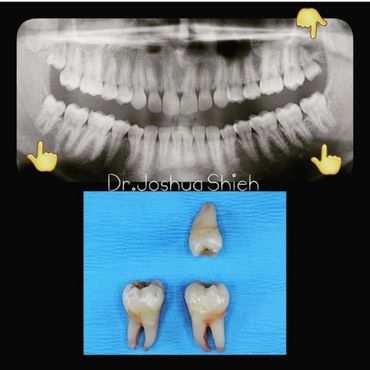

If the tooth is planned for extraction, an x-ray of the area will be taken to plan for the type of extraction.

Simple extractions are performed on erupted teeth that have regular anatomy (root and crown), and are not severely broken.